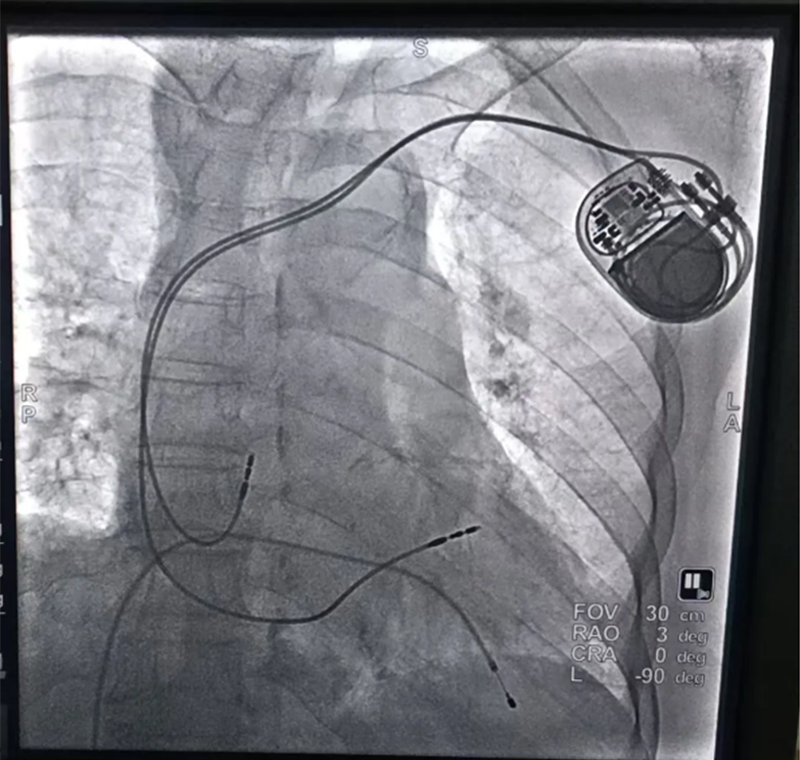

引人關(guān)注的87歲高齡王奶奶(化名),因"病態(tài)竇房結(jié)綜合征"命懸一線,心臟隨時可能停跳,傳統(tǒng)藥物治療無法解決問題。面對患者復(fù)雜病情,馬建亮主任立即組織多學(xué)科(MDT)診療,針對高齡患者血管條件差、基礎(chǔ)病復(fù)雜等特點,制定個體化手術(shù)方案,憑借其豐富的經(jīng)驗和精湛醫(yī)術(shù),成功為其植入了雙腔永久起搏器。術(shù)后,起搏器運(yùn)行穩(wěn)定,王奶奶病情平穩(wěn),未再出現(xiàn)頭暈、短暫性意識喪失、胸悶等不適癥狀。

植入雙腔永久起搏器